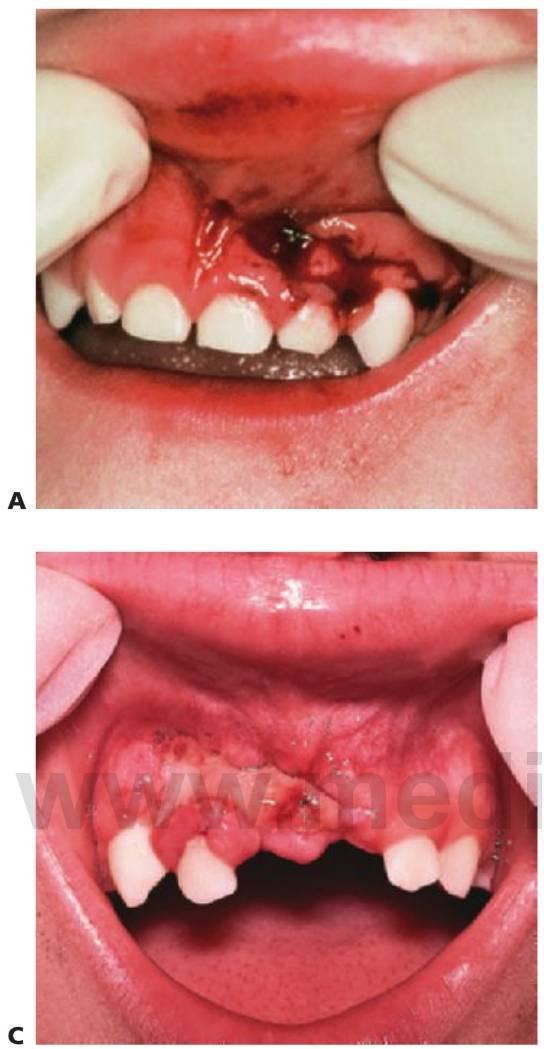

La exploración debe llevarse a cabo siguiendo un orden lógico. Resulta importante examinar todo el cuerpo, pues el paciente podría presentarse en primer lugar en la consulta del especialista dental pero haber sufrido otro tipo de lesiones (fig. 7.3 y v. cap. 1).

- Heridas extraorales y palpación del esqueleto facial (fig. 7.4).